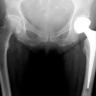

Upload Date: January 23, 2019 Full Size Image Dimensions: 256 × 197 Image Parent Post: Ημιαρθροπλαστική Ισχίου

Ημιαρθροπλαστική Ισχίου-ΑΚΤΙΝΟΓΡ